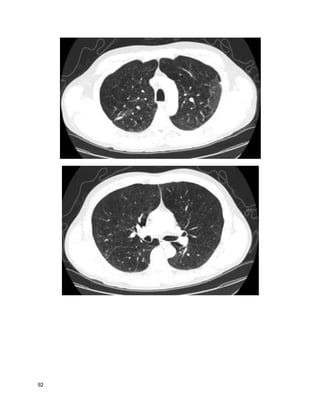

This 78 year old white woman has been coughing for "a good while"; you estimate

at least many months by her history. She is persistently fatigued, has lost 5 pounds,

but has no fevers or night sweats. She is a never-smoker. She sometimes coughs up

blood-streaked sputum. She lives in a high-rise retirement home. Other cuts of her

chest CT are similar to the one below, correlating well with the findings on chest

The primary problem is likely:

A. An infection she caught from the environment

B. An infection she caught from someone else

C. Reactivation tuberculosis

D. Bronchioloalveolar carcinoma

E. A chronic process resulting from repeated past infections

We feelthat A is the best answer.

This is a mycobacterium avium complex infection, with Lady Windemere

syndrome (bronchiectasis and multiple small nodules often involving the right

middle lobe or lingula in nonsmoking elderly women, often with chest wall or

skeletal deformities). The other options are possible but the pattern on imaging

along with the history are most suggestive of MAC, an endemic organism inhaled

from soil or water. Her bronchiectasis could perpetuate her cough and hemoptysis;

however, she also has many nodules that are indicative of ongoing infection as the

primary process.Nontuberculous mycobacteria (NTM) also include M. kansasii,

rapidly growing mycobacteria (RGM), and numerous less common species.